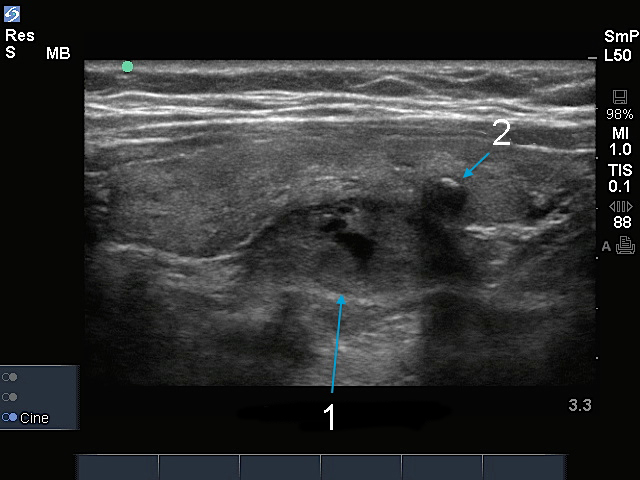

副甲状腺結節

甲状腺結節